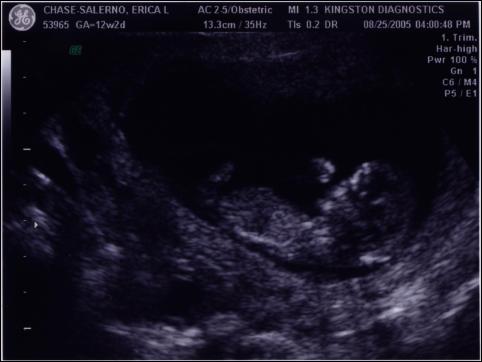

After having researched the potential effects of ultrasounds on fetuses, we decided that we would not get any routine ultrasounds this time around with the pregnancy. So, of course, we ended up having to get one after all, after some health questions came up last week.

We were thrilled to learn that everything is fine – the heartbeat was a healthy 170 beats per minute, the measurements were lined up exactly with the baby’s age (12.5 weeks on 8/24), and we discovered that we have either a thumb-sucker or a nose-picker, depending on what you can make out from the pictures. When Mike and Declan came in to see the images, the baby actually seemed to give them a little wave, and Declan waved back. Seeing the pictures seems to have made it more real for Declan that there’s an actual “baby” in there.

Here are two of the images we got that day – enjoy the world’s first look at Baby #2!